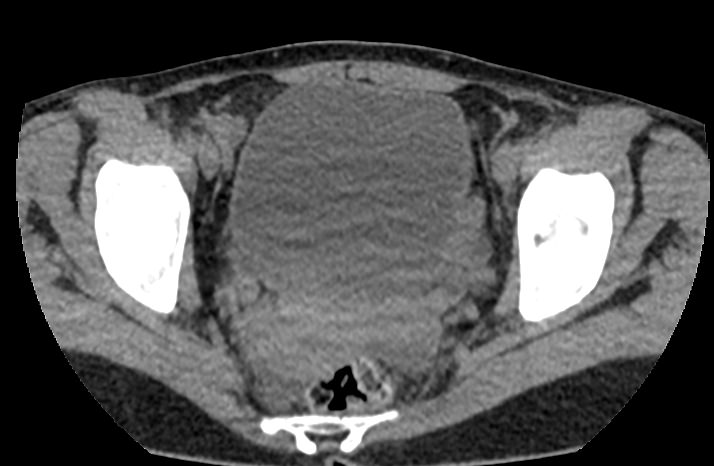

Мультиспиральная КТ мочевого пузыря является частью протокола обследования органов малого таза. Это высокоинформативный рентгенологический метод исследования, позволяющий детально визуализировать мочевой пузырь, нижнюю часть мочеточников, внутренние половые органы, прямую кишку.

Зачастую подобное исследование проводится при мочекаменной болезни (МКБ) для выявления конкрементов, определения их положения, размеров и плотности. Локализация конкремента существенно влияет на терапевтическое лечение МКБ, а наличие дивертикулов стенки мочевого пузыря на возможность самостоятельного выхода камня.

Также при данном исследовании возможно выявить утолщение стенки мочевого пузыря, что при диффузных изменениях может соответствовать проявлениям цистита, а локальные или неравномерные утолщения – характеризовать патологический процесс обусловленный новообразованиями.

Для улучшения визуализации патологических образований, в частности, при подозрении на опухолевый процесс, проводится внутривенное болюсное контрастирование. Методика контрастного усиления основана на введении в вену контрастного препарата, который в большей степени накапливается в патологически измененных участках и обеспечивает их яркую визуализацию на фоне здоровых тканей. Контрастирование дает возможность определить врачу границы опухоли, оценить степень прорастания в соседние органы и ткани, выявить опухоли минимальных размеров (как первичного, так и метастатического характера).

Что позволяет увидеть КТ мочевого пузыря

- цистит;

- дивертикулы мочевого пузыря

- цистоцеле

- уретероцеле

- варианты строения мочеточников

- камни мочевого пузыря;

- травмы, разрывы и растяжения органа;

- опухолевые новообразования.